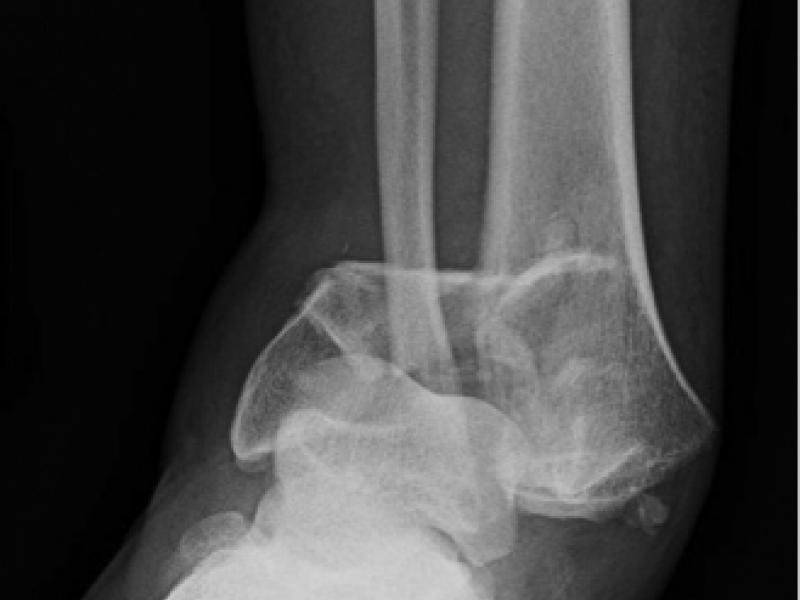

What's the diagnosis?  By Dr. Erica Schramm

January 06 2021

A 48 year old male fell from a ladder landing on his right